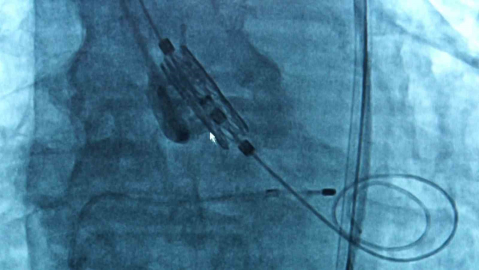

"İlerleyerek kalp yetmezliğine kadar gitmekte"

TAVI yöntemine ilişkin bilgi veren Doç. Dr. Dilay Karabulut, "Aort kapak, kalpten çıkan ana damar dediğimiz aortun ağzındaki kapak. Yaşla beraber kapakta gelişen kireçlenme ve kalsifikasyon((Vücut dokusunda kalsiyum birikmesi)a bağlı olarak kapaklar birbirine yapışmakta ve kapak alanı daralmaktadır. Bunun sonucunda kalp yeteri kadar kanı vücuda pompalayamadığı için hastada birtakım semptomlar gelişmekte, bu ilerleyerek kalp yetmezliğine kadar gitmekte. Kapak daraldığı zaman 2 tane tedavi yöntemimiz var; kapağın cerrahi olarak çıkarılması ya da TAVI dediğimiz yani kasıktan küçük bir kesi yapılarak kapağı yerleştirdiğimiz bir işlem. Eskiden daha çok cerrahi işlemler ön plandaydı. Ne yapıyorduk; hastanın göğüs kafesi açılıyor, kalbi durduruluyor, kapak yerinden çıkarılıyor ve yapay bir kapak takılıyordu. Şu an hala bazı seçilmiş hastalarda cerrahi aort kapak replasmanı yapılıyor ancak TAVI işlemi 20 yıldır tüm dünyada, ülkemizde de aynı şekilde yapılan bir işlem. Hasta için daha konforlu özellikle seçilmiş hasta gruplarında hastaneye yatış süresi daha kısa, hastanın göğüs kafesi açılmadan, kalbi durdurulmadan ve hastanede işlem sonrası yaklaşık 1 gün kadar kalıp hastayı taburcu ediyoruz. Nasıl yapıyoruz; kasıktan küçük bir kesi açıyoruz, bu kesiden bir telle kalbin içine doğru ilerliyoruz. Aort kapağın olduğu yere yeni yapay kapağı yerleştiriyoruz. Operasyon yaklaşık 1 saat kadar sürüyor. Yapılan çalışmalarla gösterildi ki artık orta risk hatta son zamanlarda düşük riskli olan grupta da TAVI işlemini yapabiliyoruz. Yapay kapaklar olduğu için tabi ki ilerleyen dönemlerde dejenerasyona uğrayabiliyor ama 10-15 yıllık takiplerde şu ana kadar çok olumsuz bir gelişme gösterilememiş" dedi.